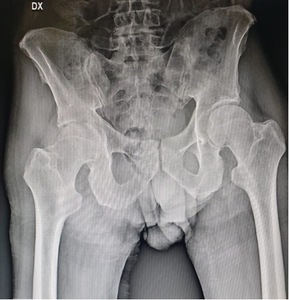

A 50-year-old male patient, working as a carpenter, presented to our attention with a one’s week history of acute right hip pain following a minor accidental hip hyperabduction injury. The patient presented with intense pain and was barely able to maintain upright posture. Past medical history was non-contributory, patient did not smoke and denied alcohol and recreational drug abuse. He had been taking pain medications and NSAIDs since the onset of the pain with no significant benefit. At this his current admission, physical examination showed soft tissue oedema around the right hip, no skin erythema, limited internal rotation of the hip joint or range of motion of the hip. Log-roll, Straight-leg-raise and Patrick test clinical test were positive. The most important clinical sign was the high grade of pain with an inability to bear weight without rest remission. There was no fever during the previous days and at the admission. Patient was admitted to our hospital where X-ray examination of the hip (Fig. 1) and laboratory tests were performed.

Given the negativity of both tests, an MRI of the lumbar spine and pelvis was performed: both examinations resulted negative. Patient was prescribed rest, analgesia, and periodic check-ups were scheduled. After 30 days the patient returned to our observation with unchanged symptoms but with the addition of a fever of 39° C lasting 48 hours, three days before the follow-up appointment. Repeat laboratory tests were significant respectively for a white blood cell count of 35.5 x 109/L, increased inflammatory markers with an erythrocyte sedimentation rate (ESR) of 97.0 mm/h and a C-reactive protein (CRP) of 47.8 mg/L.